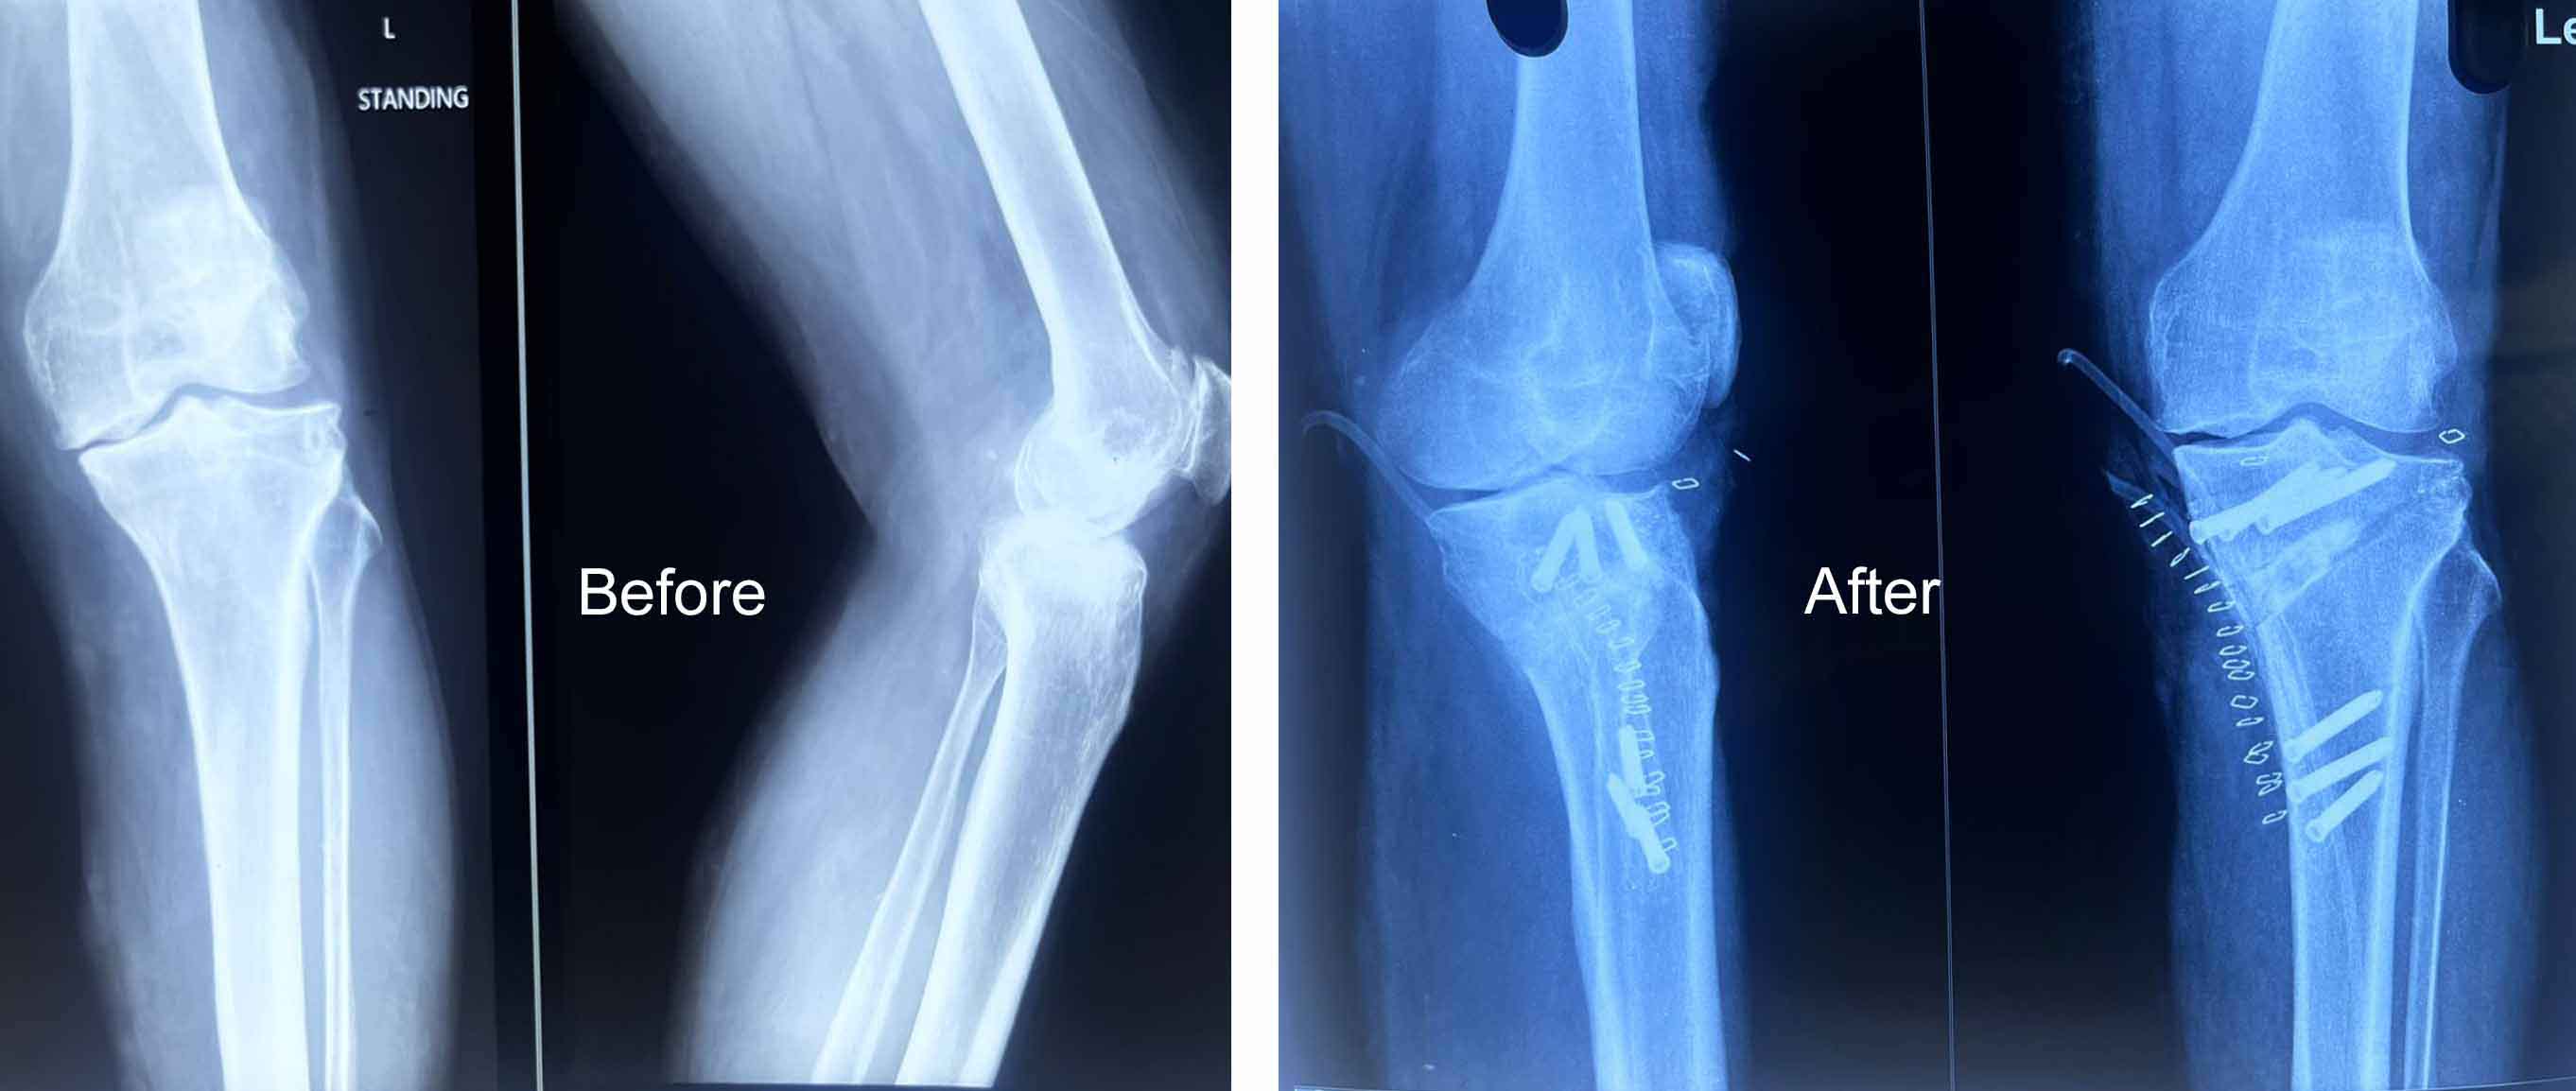

Orthopedic Care